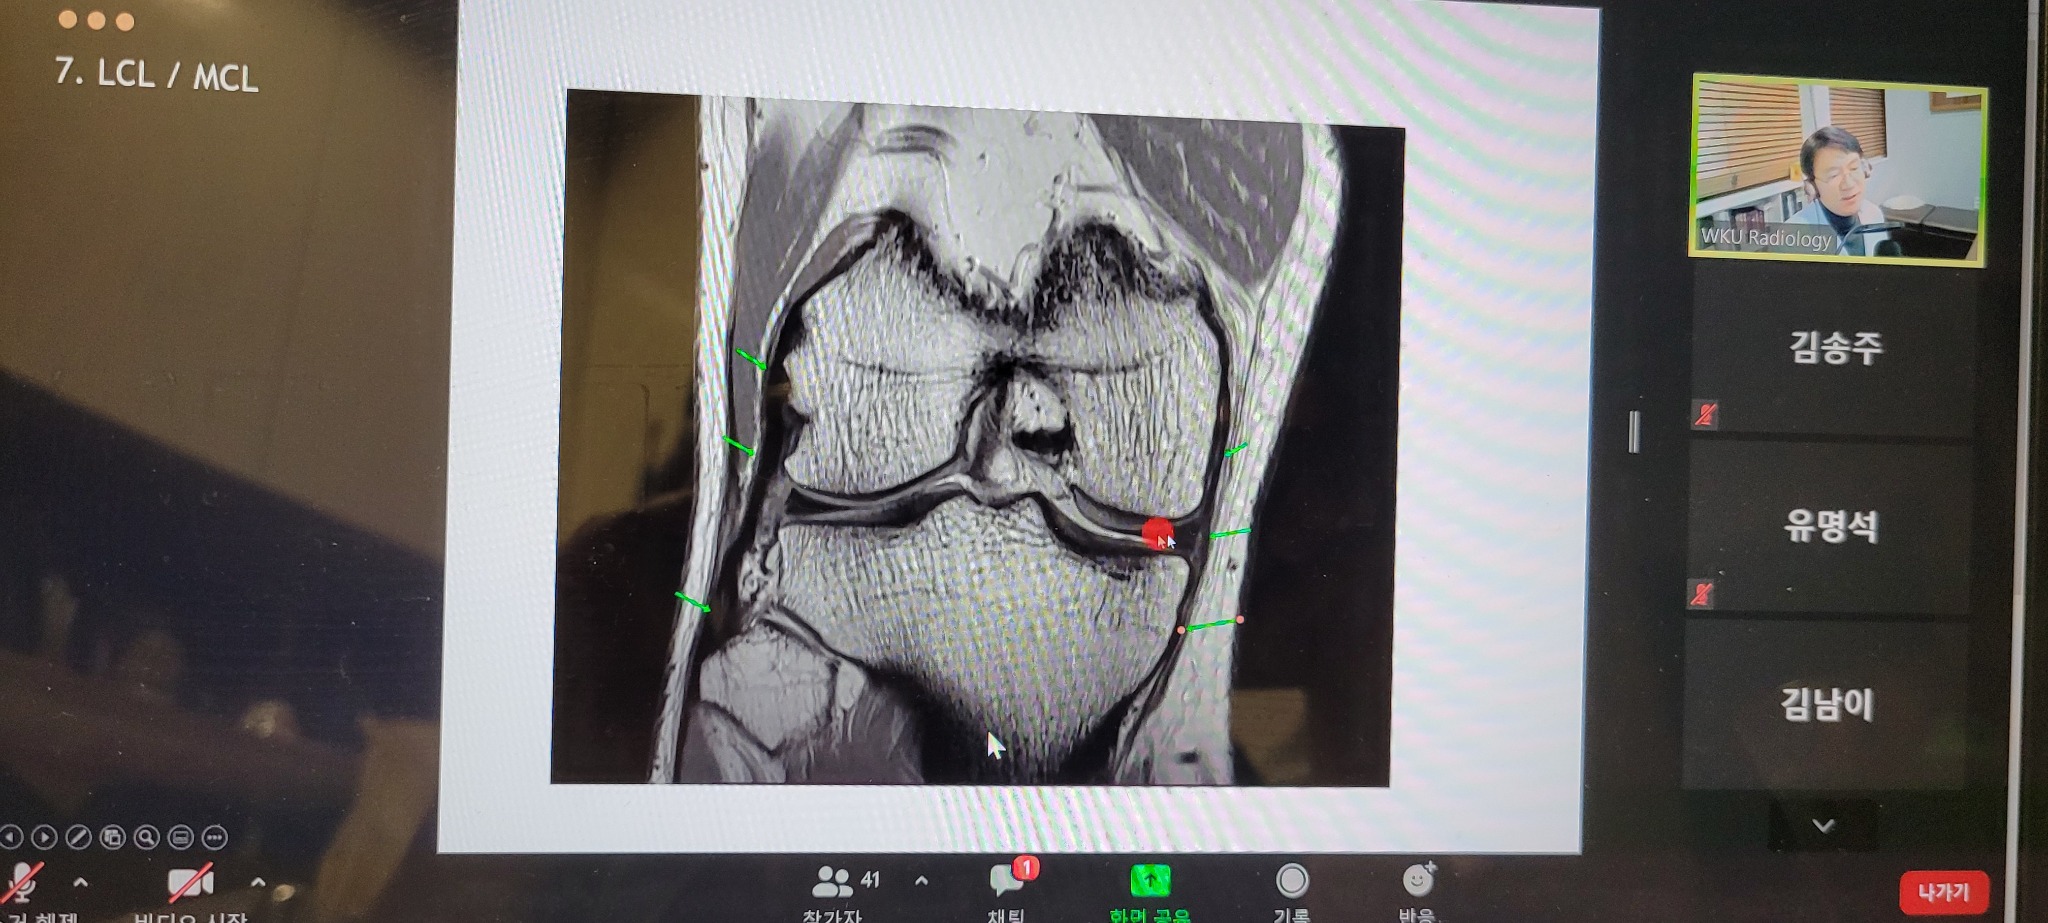

11일 개최된 보수교육에서는 우석대·원광대 한의과대학에서 영상의학 수업을 담당하고 있는 한의영상의학회 신민섭 학술교육부회장이 ‘Knee MRI Approaching’을 주제로 강연을 진행했다.

이날 신 부회장은 “무릎관절은 우리 몸에서 가장 큰 윤활관절로, 연부조직과 결합조직의 외상 혹은 퇴행에 의한 손상이 많이 발생하는 부분”이라며 “임상에서 환자들이 ‘무릎연골이 찢어졌다는데 침 치료하면 나을수 있을까요?’라는 질문을 하곤 하는데, 관절연골의 재생이라는 측면은 그리 쉬운 문제가 아님에도 불구하고 관절의 기능을 회복시키는 치료는 다분히 한의학적 치료와의 연관성이 확실하다”고 강조했다.

즉 무릎 손상에서 중요한 관건은 섬유연골의 tear(찢김·파열)이냐 degeneration(퇴행)이냐를 판단하는 것이 필요한데, 의학적 영상정보의 독점으로 인해 환자에게 수술적 방법을 권하는 폐해가 발생할 수 있고, 환자 또한 연골의 파열이라는 표현에 어쩔 수 없이 수술을 불가피하게 인식하게 되는 오류가 있는 상황에서 한의사들이 보다 적극적으로 MRI 영상에 대한 이해와 판독을 통해 환자에게 치료의 선택권을 넓혀줄 수 있는 계기를 마련할 수 있다는 것.

특히 신 부회장은 “임상증상에 따른 수술적 혹은 비수술적 요법이 선택되어질 수 있지만, 무릎관절을 구성하는 연부조직의 병증을 MRI를 통해 확인하는 한편 치료의 목표점을 한의학적 치료, 특히 연부조직학회의 장점인 도침을 활용함으로써 한의임상의 외연을 넓히는 치료방식의 해법이 될 수 있다”고 강조했다.